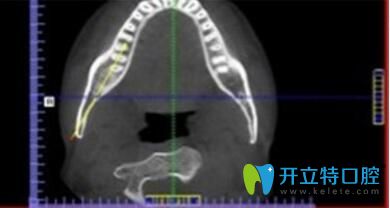

? 1、詳細測量數(shù)據(jù):

? 采用診療標準,在制定精細的矯正方案前,必須通過數(shù)字化診療,集全景,頭顱、CBCT功能于一體,能夠精準定位頭顱數(shù)據(jù)采集,提供高清晰度3D診斷圖片,采集口腔全景數(shù)據(jù),提高治療效果,因此牙齒將準確的向設計好的方向移動,呈現(xiàn)更美的口腔弧度。

長沙美萊口腔牙齒矯正優(yōu)勢詳細測量數(shù)據(jù)